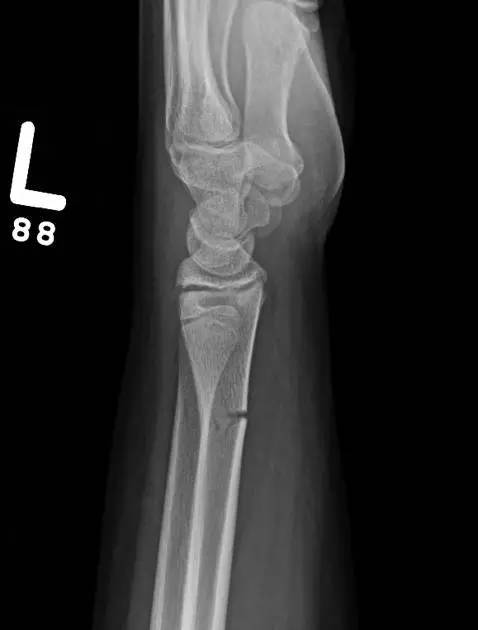

9. Essex-Lopresti 骨折

是桡骨头骨折伴有下尺桡关节脱位,导致骨间膜损伤,桡骨短缩。此种损伤,桡骨头骨折的诊断往往是明确的,容易忽视的是下尺桡关节脱位,特别是早期,下尺桡关节的症状不明显,X 线表示也不明显。

Essex-Lopresti 损伤。前后位(A)和侧位(B)示桡骨头关节内骨折(白色实线箭头);(C~E)伤后 1 个月复诊,患者诉腕关节疼痛,X 线(C,D)发现下尺桡关节脱位,(E)CT 进一步证实损伤的存在 (来源:Radiol Clin North Am. 2015 Jul;53(4):717-36)